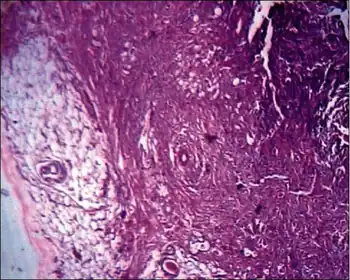

Histopathological examination of spindle cell lipoma